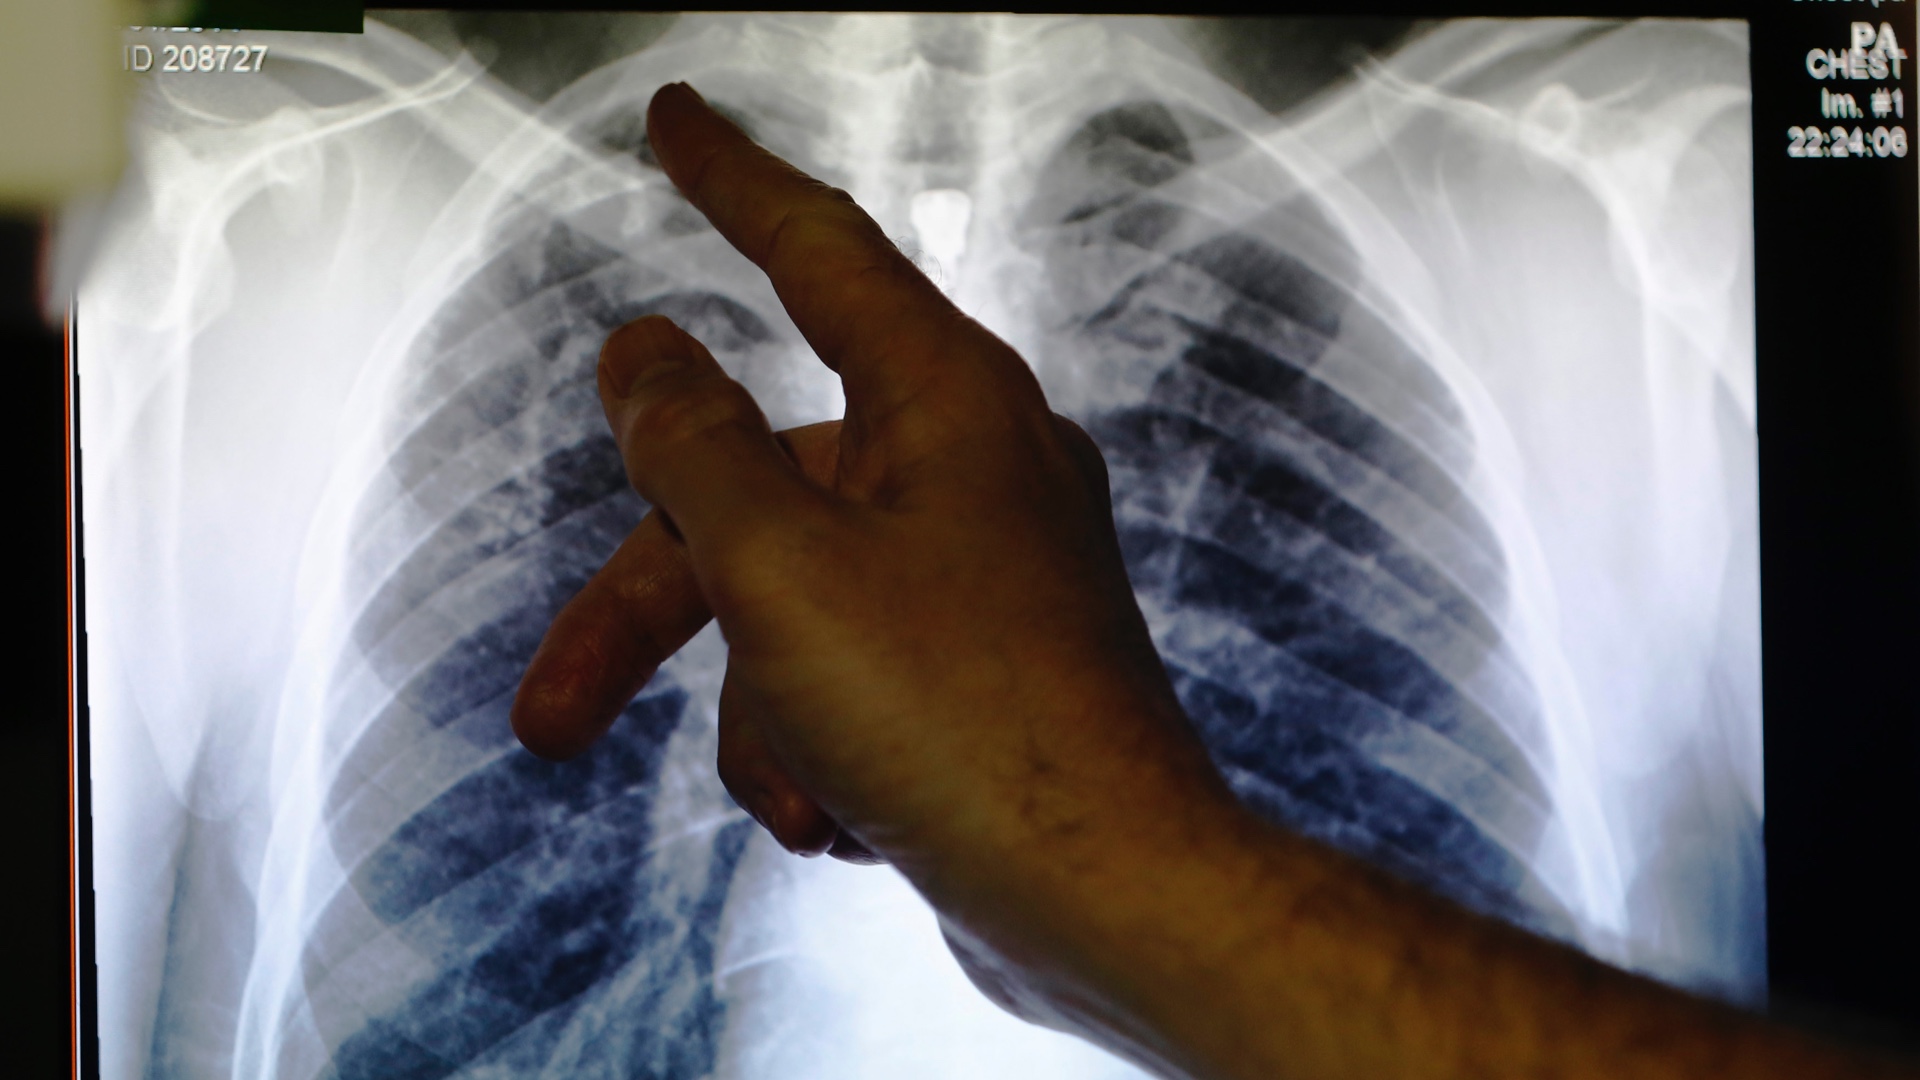

Lungs

It is clear that people with only mild symptoms (usually a dry cough and fever) will make a full recovery without any long-lasting damage to their bodies, but some scientists believe evidence is mounting to show that those on the moderate to severe end of the spectrum (who experience breathing difficulties and pneumonia) may be left with permanent lung damage.

When coronavirus enters the body, it does so via the respiratory tract. Here it behaves like other coronaviruses, such as severe acute respiratory syndrome (SARS), which the World Health Organization (WHO) reported typically attacked the lungs in three phases: Viral replication, immune hyper-reactivity and pulmonary (lung) destruction.

At this point, COVID-19 can trigger an exaggerated immune response setting off a chain reaction which causes increased inflammation and fluid to fill the lungs. This affects approximately 14 percent of infected people. When this happens, pneumonia sets in as the fluid attracts bacteria as well as the virus itself. Breathing becomes difficult and patients need to be put on a ventilator.

It is this process of excess inflammation brought on by an overreacting immune system that is the biggest danger to the lungs. It can cause irreversible damage to the air sacs on the periphery of the lungs known as alveoli. These are delicate balloon-like structures which fill with air when we take a breath in and allow the oxygen to pass from the lungs into the blood for transportation to the rest of the body. They also help take carbon dioxide away.

The inflammation caused by the body’s immune response to the virus can cause the alveoli to pop, giving the lungs a honeycomb-type appearance, or to harden so they are no longer able to do their job. When this happens, a condition similar to fibrosis or hardening of the lungs occurs.